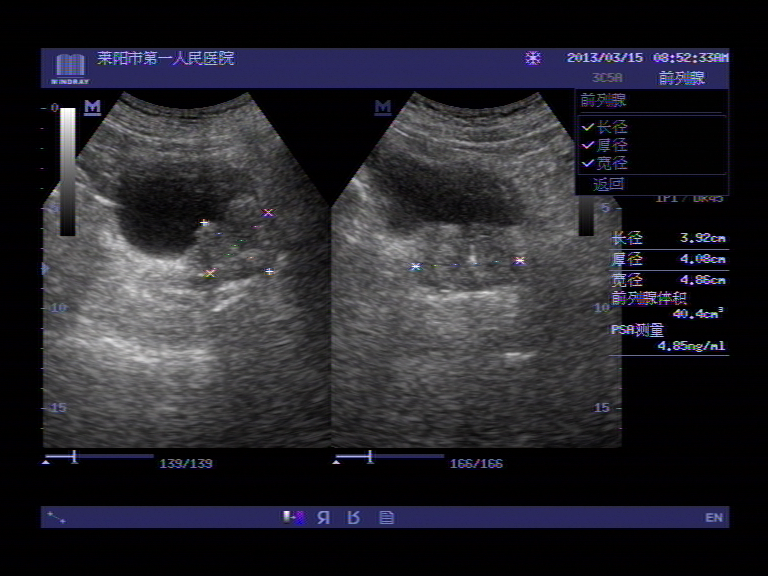

超声入门贴41膀胱癌

图片尺寸768x576